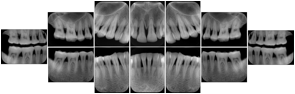

2. A patient requests cosmetic surgery to enhance their facial appearance. The case requires consultation between an orthodontist in New York and an oral surgeon in California. The cephalometric series of 2D projections constructed from the volumetric CT data that is used for the discussion is arranged by a Structured Display for transfer between the two practitioners.

Cephalometric Series Structured Display

Figure OO-2. Cephalometric Series Structured Display